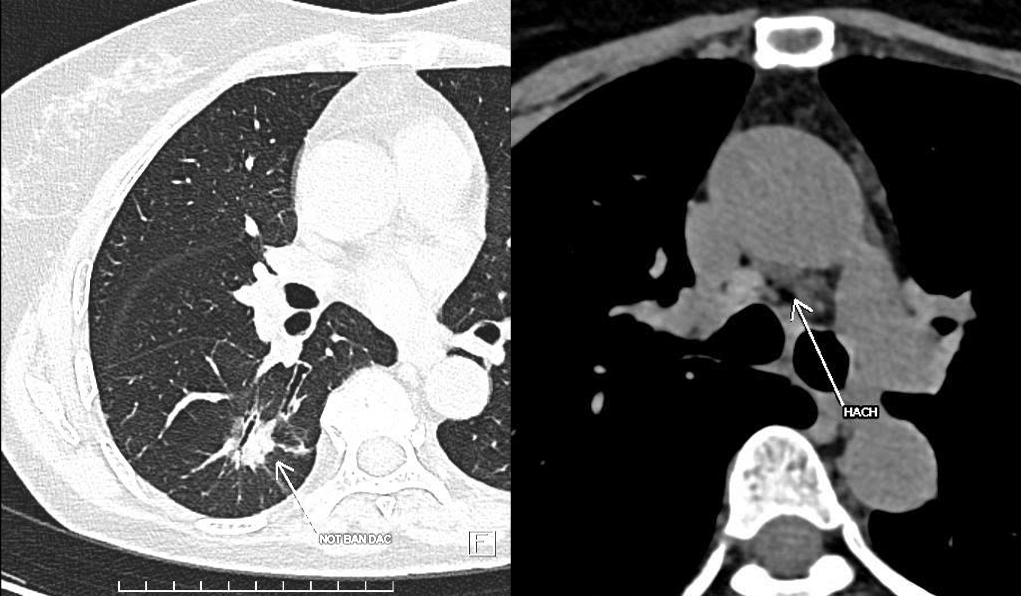

Three months prior, Lan was diagnosed with stage 3A lung cancer with lymph node metastasis at a local hospital and advised to undergo long-term systemic chemotherapy. Seeking a second opinion at Tam Anh General Hospital in Hanoi, a CT scan revealed a small, nearly 2 cm tumor in her right lower lung lobe. The mediastinal and subcarinal lymph nodes (where the right and left bronchi divide) appeared flat, with regular borders, and retained their normal structure.

Dr. Vu Huu Khiem, Head of the Oncology Department, explained that the lymph nodes hadn't been infiltrated because the images showed regular borders, suggesting a high probability of early-stage, 1A lung cancer. Lan was scheduled for minimally invasive surgery to remove the lower lobe of her right lung, along with mediastinal lymph node dissection.

The lung tumor and lymph nodes on Lan's CT scan. Photo: *Tam Anh General Hospital*

The surgical team removed the lower right lung lobe containing the solid tumor and dissected 11 surrounding lymph nodes, sending them to the Anatomic Pathology and Cell Biology Center. Results confirmed early-stage lung adenocarcinoma, with 11 out of 11 lymph nodes showing inflammation, not metastasis.